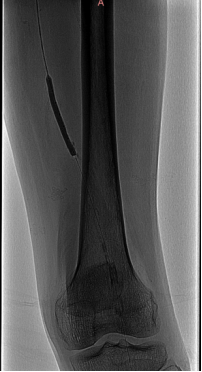

★ 管腔准备

引入Shockwave IVL M5(7.0×60mm)分别扩张双髂总动脉(将球囊充盈至4atm后,激发震波,在完成一组脉冲后,将球囊缓慢充盈至6atm并持续60秒)

★ 术后造影

左右髂外动脉狭窄明显好转

★ 术后CTA

显示钙化病变重塑,双侧髂动脉管腔较前明显改善